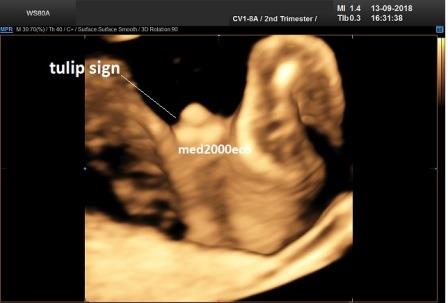

Diagnosi ecografica prenatale

La diagnosi ecografica prenatale è solo di sospetto. Le caratteristiche ecografiche prenatali possono essere caratterizzate da:

Meizner I. The 'tulip sign': a sonographic clue for in-utero diagnosis of

severe hypospadias.Ultrasound Obstet Gynecol. 2002; 19(3):317.